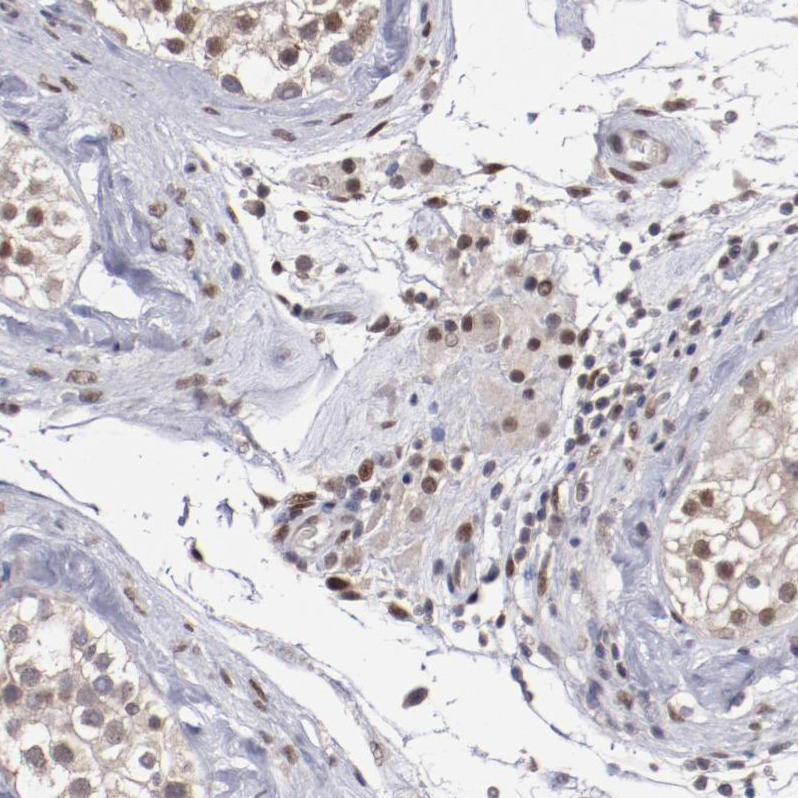

Immunohistochemical staining of human placenta shows strong nuclear positivity in trophoblastic cells.